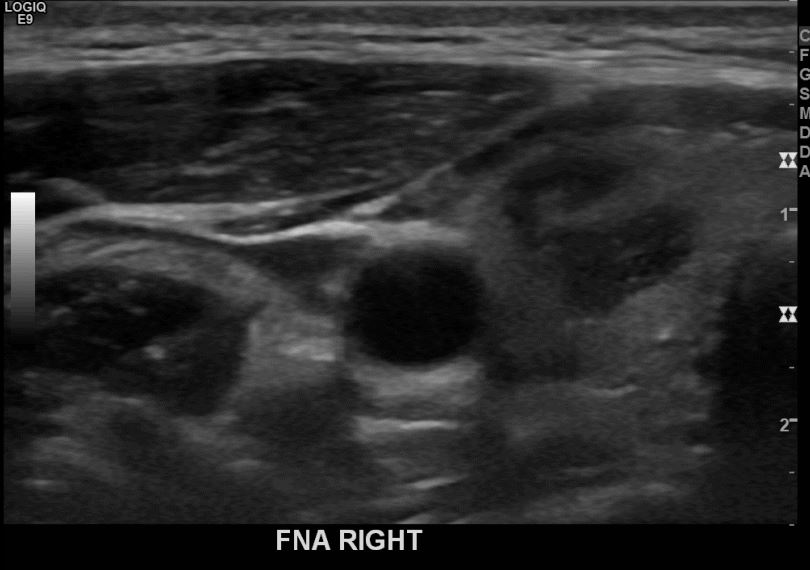

상기환자  외부검사이상소견으로 내원하신 40대 초반 여성분으로 의심스러운 우엽혹 세포검사진행후 갑상선암으로 진단되었습니다